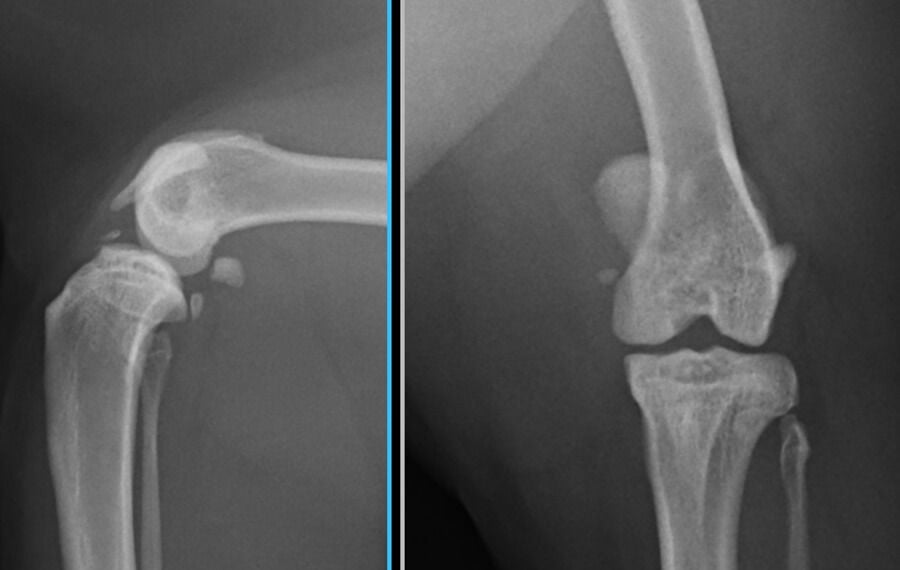

Patellar luxation is one of the most common orthopaedic conditions in dogs. In simple terms, it occurs when the patella (kneecap) dislocates or "pops out" of the trochlear groove, the natural track at the end of the thigh bone.

The knee is a complex mechanism where bones, tendons, and muscles must work in perfect unison. If there is a malalignment in the bones above or below the knee, the patella can dislocate. While common in small breeds like Terriers and Miniature Poodles, it is also frequently diagnosed in larger breeds such as Labradors.

Whether the dislocation is intermittent or permanent, the condition causes significant discomfort and predisposes the joint to osteoarthritis (OA). Over time, the repeated luxation wears away the protective cartilage on the underside of the patella, leading to chronic pain and inflammation.

Femoral Trochlear Sulcoplasty: Deepening the groove the patella sits in to create a secure "nest."

Tibial Tuberosity Transposition (TTT): Realigning the patellar tendon attachment point on the shin bone. This is a critical step to ensure the quadriceps pull the kneecap in a straight line, preventing recurrence.